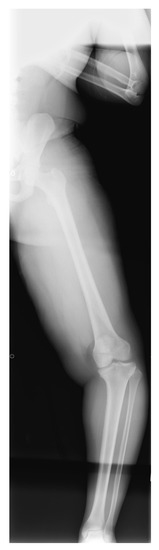

3. ITV Differential Diagnosis and Clinical Features

4. Radiographic Imaging

5. Radiographic Analysis